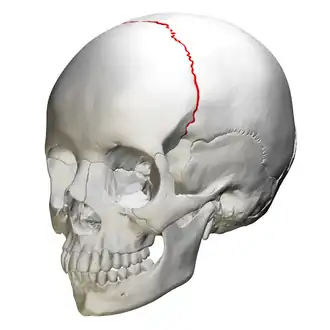

![]() Anterolateral view of coronal suture (red) | |

The coronal suture is a dense, fibrous connective tissue joint that separates the two parietal bones from the frontal bone of the skull.

The coronal suture lies between the paired parietal bones and the frontal bone of the skull.[1] It runs from the pterion on each side.